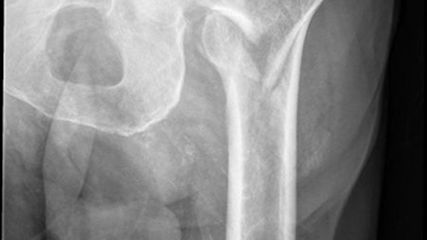

Abb. 3: Pertrochantäre Fraktur